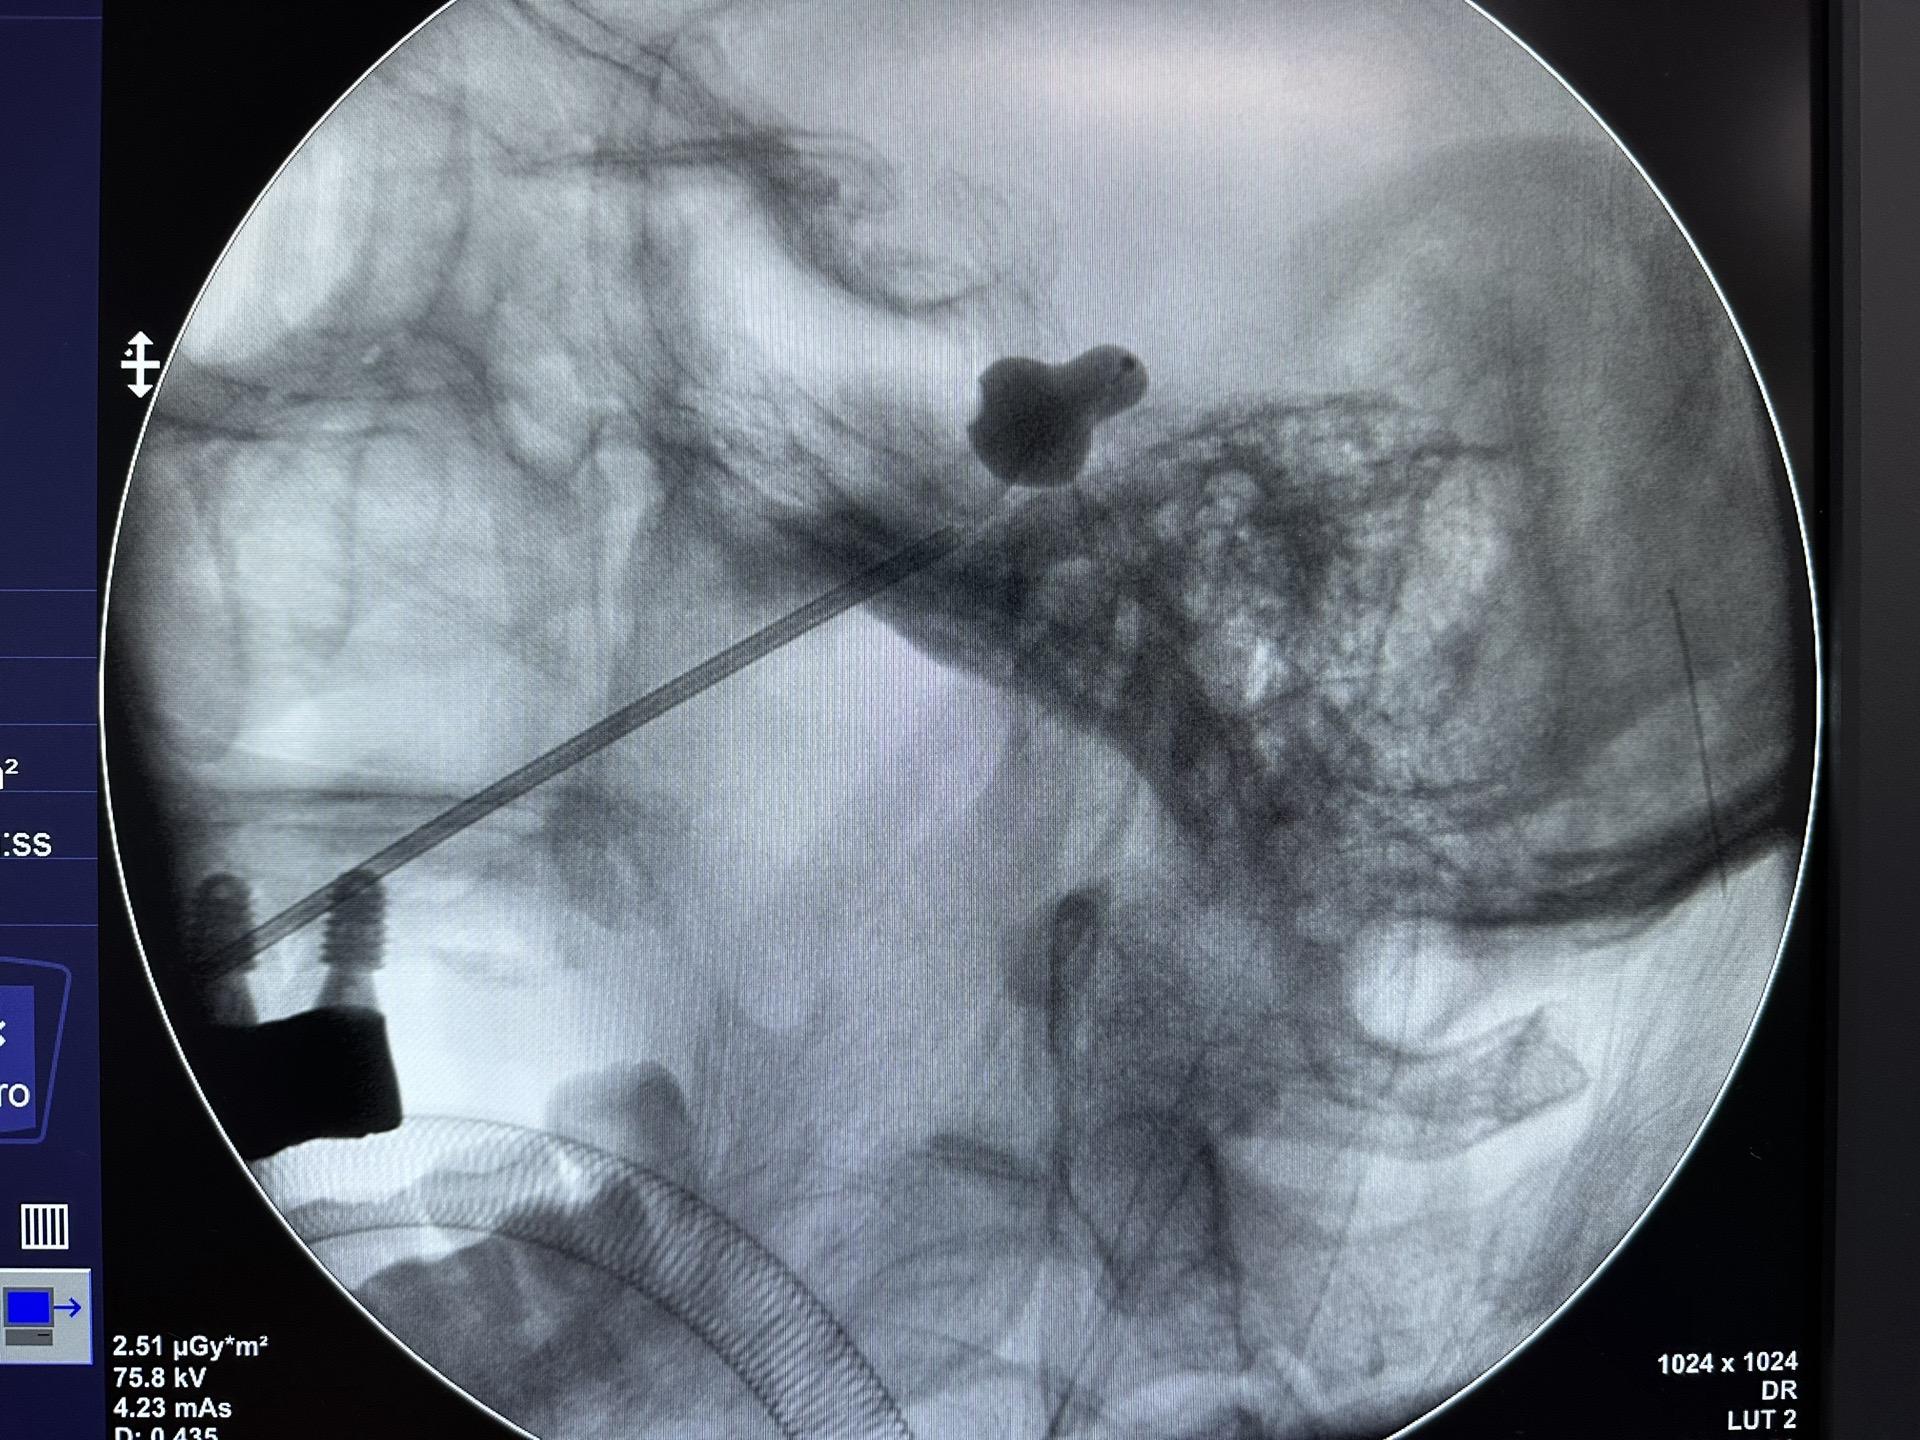

🏓型---痛!痛!痛!痛!痛!痛! 三叉神经痛球囊手术日常,如果身体条件较一般,或者其他原因不能耐受开颅的可以作为其中一个选择!